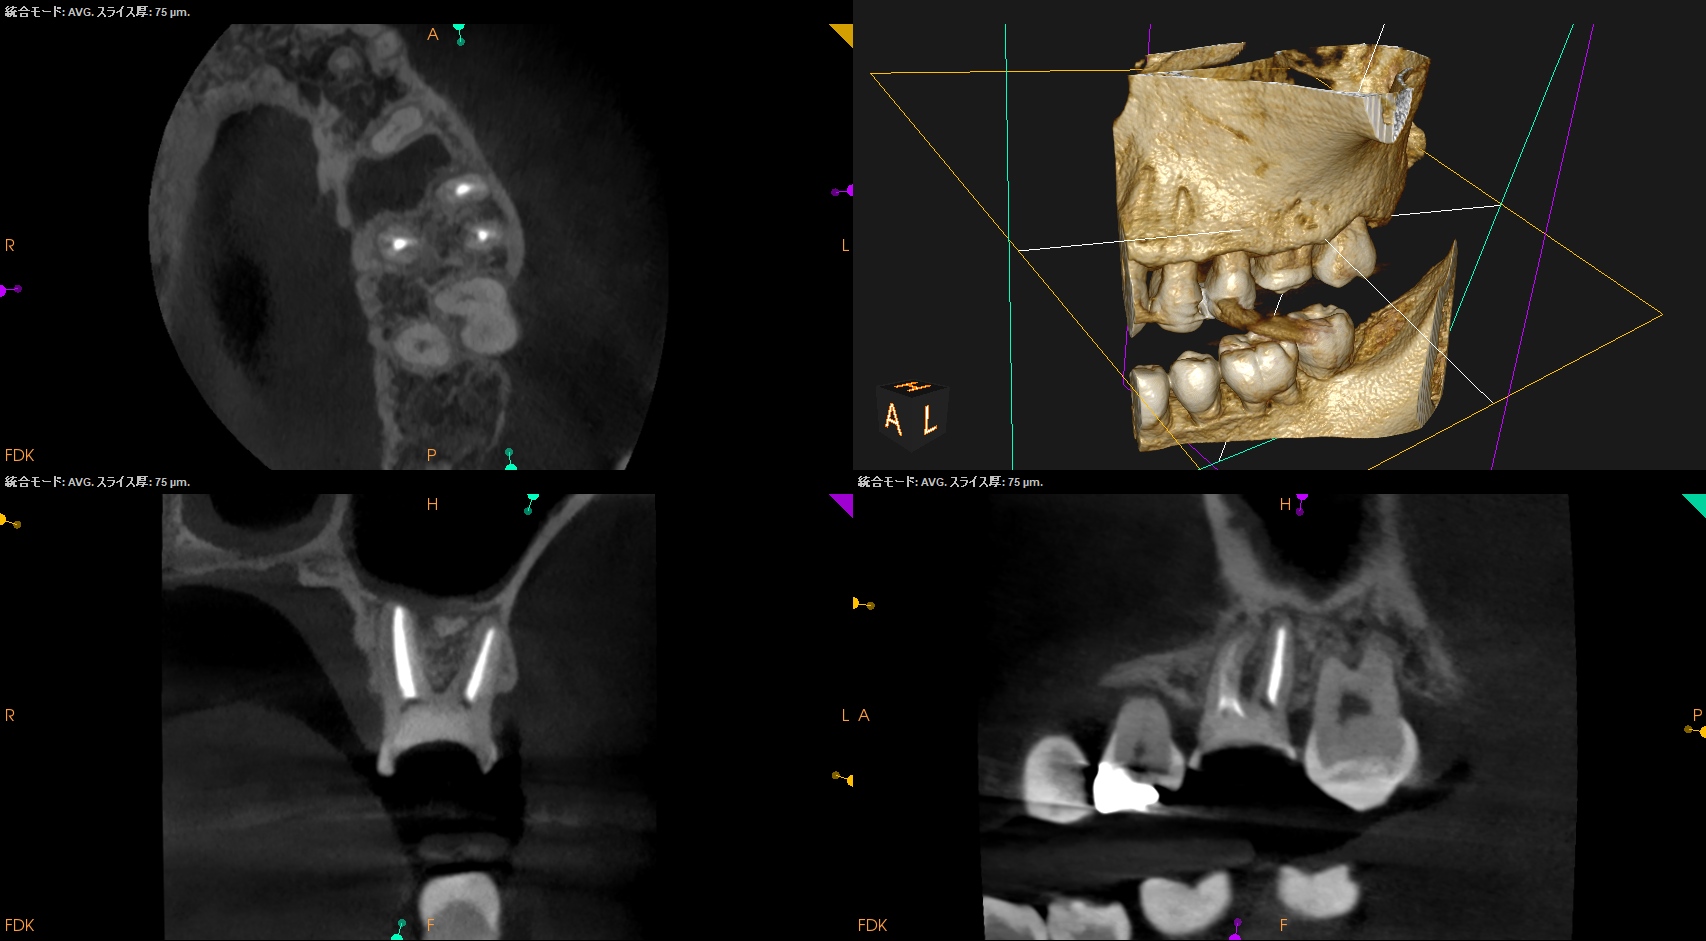

CBCT(2025.4.15)

MB

MBの根管口部あたりに穿孔が疑われる所見がある。

ストリッピングパーフォレーションというやつだ。

根充後に根管をBC Puttyで埋める必要があるだろう。

DB

P

DB,Pには何もない。

SelectiveにMBのみを扱う治療になるだろう。

さて、外科の際は

上顎洞の穿孔を避けるため、MBはCEJよりも5.6mm下方に1.3mm Osteotomyして頬舌的に4.3〜4.9mm切断する必要がある。

これはそれほど困難ではない。

その後、Root tipごと取り出す形になるだろう。